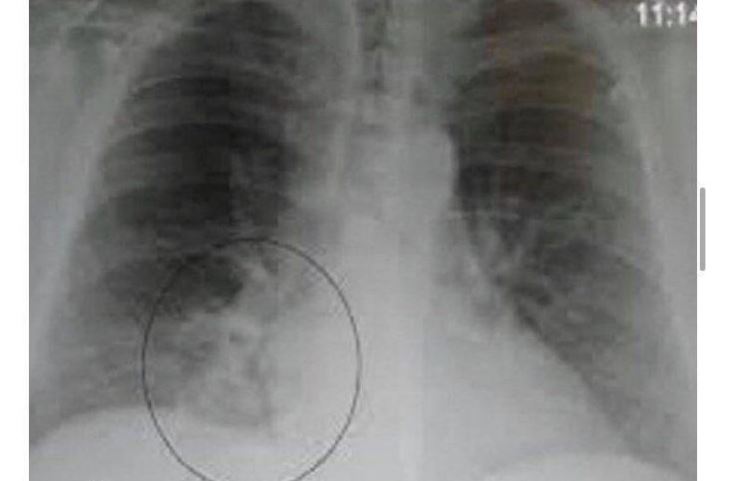

Osim toga, praziluk blagotvorno utiče na pluća, probavu, jetru, bubrege i cirkulaciju, pomaže u iskašljavanju i ublažavanju simptoma astme i upale pluća. Takođe, doprinosi regulaciji holesterola i boljem radu bubrega.